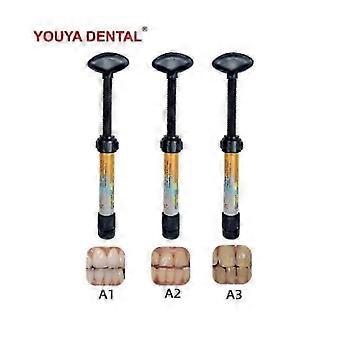

Teeth Resin Tooth Repair Dental Cement Cavity Filling Strong Repair Restoration

Teeth Resin Tooth Repair Dental Cement Cavity Filling Strong Repair Restoration

Teeth Resin Tooth Repair Dental Cement Cavity Filling Strong Repair Restoration

- Kategoriye Göre: Diş Sementleri

Beden: A1